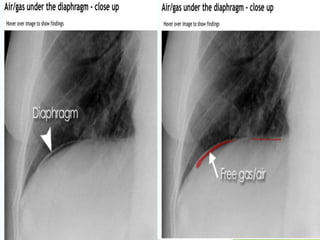

Abdominal X-ray

 Although the erect chest X-ray is a much more

sensitive investigation for pneumoperitoneum,

there are several signs that may be useful in

detecting free gas on an abdominal X-ray.